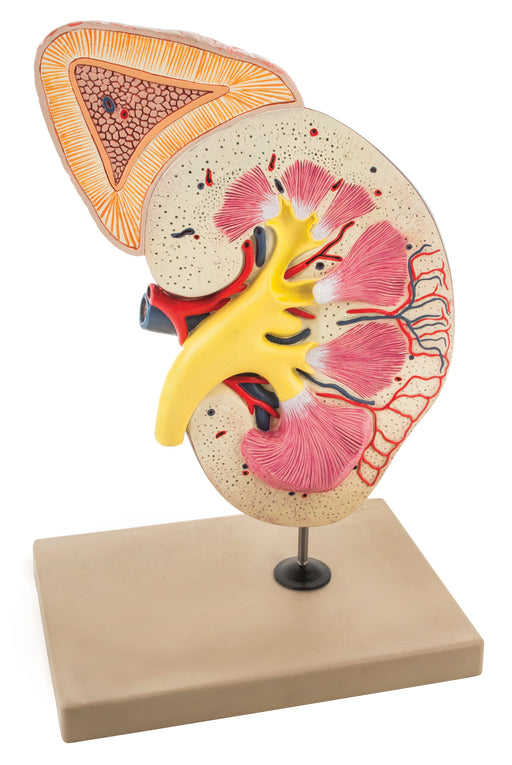

Kidney Model, Longitudinal Section - Right

Longitudinal section of the right kidney model shows kidney glomerulus, tubes, one collection tube, pyramids, kidneys orifice system, kidney pelvic...

View full detailsAM16059 -